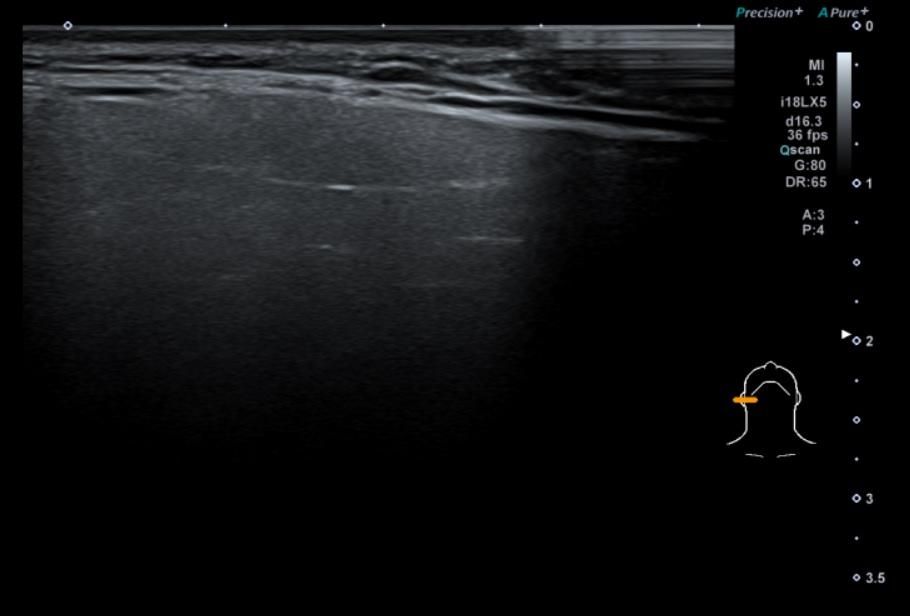

• 1번 째 사진